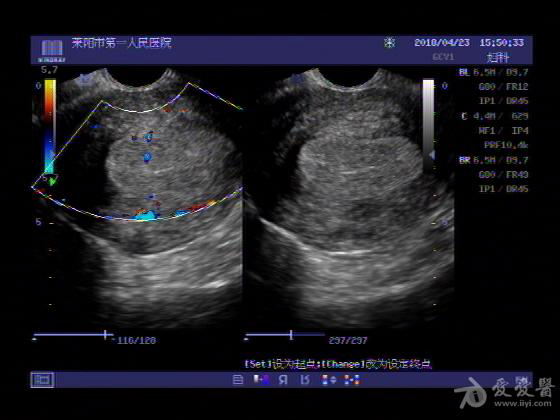

女,48岁,月经量多,两个月,一年前出现过类似现象,刮宫吃药后缓解。

超声可见:子宫内膜显著增厚,后肌壁内膜可见范围约3.27X0.90CM低回声区,CDFI显示较丰富线样血流,宫底宫腔内见类**状低回声结节。前肌壁见多发类圆形低回声结节。

超声提示:子宫内膜增厚(建议刮宫病理),子宫多发肌瘤

病理结果:内膜增生